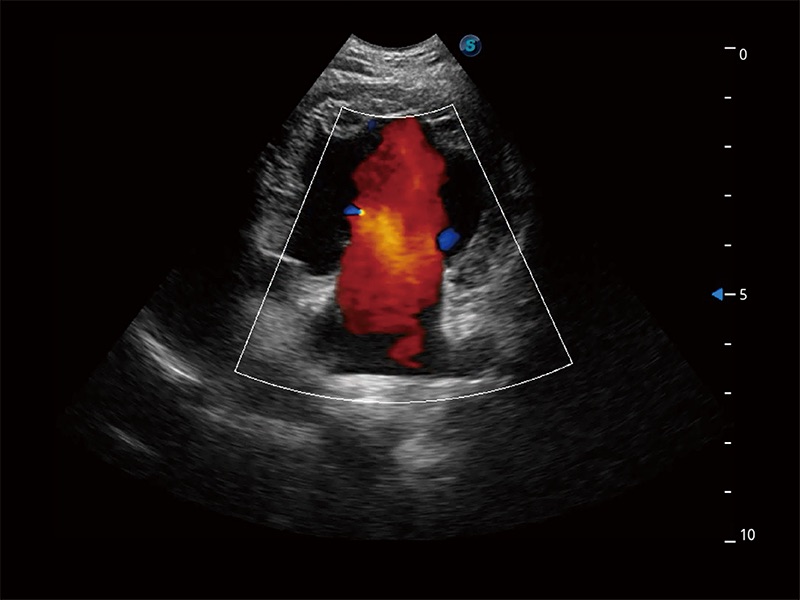

(犬)四腔心MQA

(犬)二腔心血流